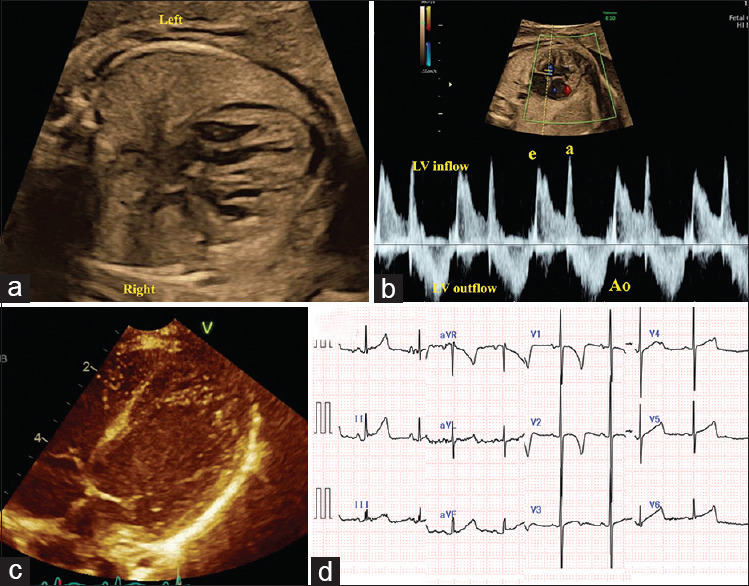

A 35-year-old pregnant woman was referred to our hospital because of fetal bradycardia. Fetal echocardiography revealed a normal fetal heart except for slightly prominent trabeculae in the left ventricle, normal cardiac function, and fetal sinus bradycardia with a heart rate of 100 bpm. Electrocardiography (ECG) after birth revealed sinus bradycardia with a heart rate of 70-80 bpm. Transthoracic echocardiography revealed left ventricular noncompaction localized in the apex with normal cardiac function. A 24-h Holter ECG showed a heart rate range of 62-169 bpm without a pause of more than 2 s. A genome analysis performed during the neonatal period revealed a heterozygous inflame variant p.(Ser672_Asp676del)[chr15:g. 73324203_733242] in HCN4 gene. Fetuses with a heart rate less than the 3rd percentile of the gestational age should be followed and screened for congenital heart disease and cardiomyopathy. In addition, inherited arrhythmia syndrome should be considered.